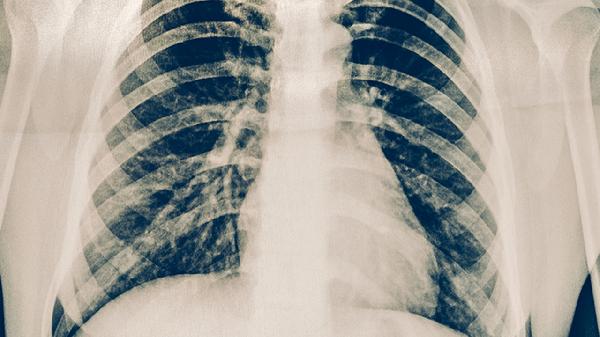

2、肺大泡破裂的典型症状包括突发胸痛、呼吸困难、咳嗽和心跳加快。如果出现这些症状,应立即就医,医生会通过胸部X光或CT检查确诊。